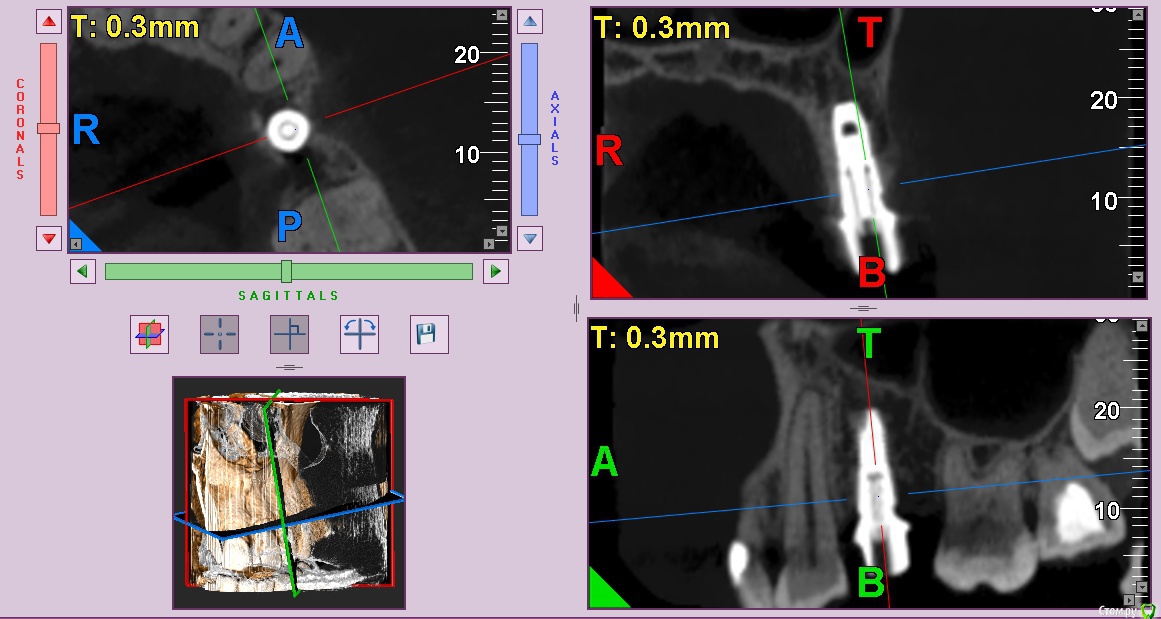

колесников Опубликовано 12 июня, 2017 Автор Поделиться Опубликовано 12 июня, 2017 Контрольное кт спустя 3 мес. Откуда-то наросло 2мм у шейки. Ссылка на комментарий

Doctor Vlad Опубликовано 13 июня, 2017 Поделиться Опубликовано 13 июня, 2017 Откуда-то наросло 2мм у шейки. да видимо графт был, причем не коллапон коллагеновый а костная стружка, даже по первым снимкам после операции там чтото рыхлое торчит. Ссылка на комментарий